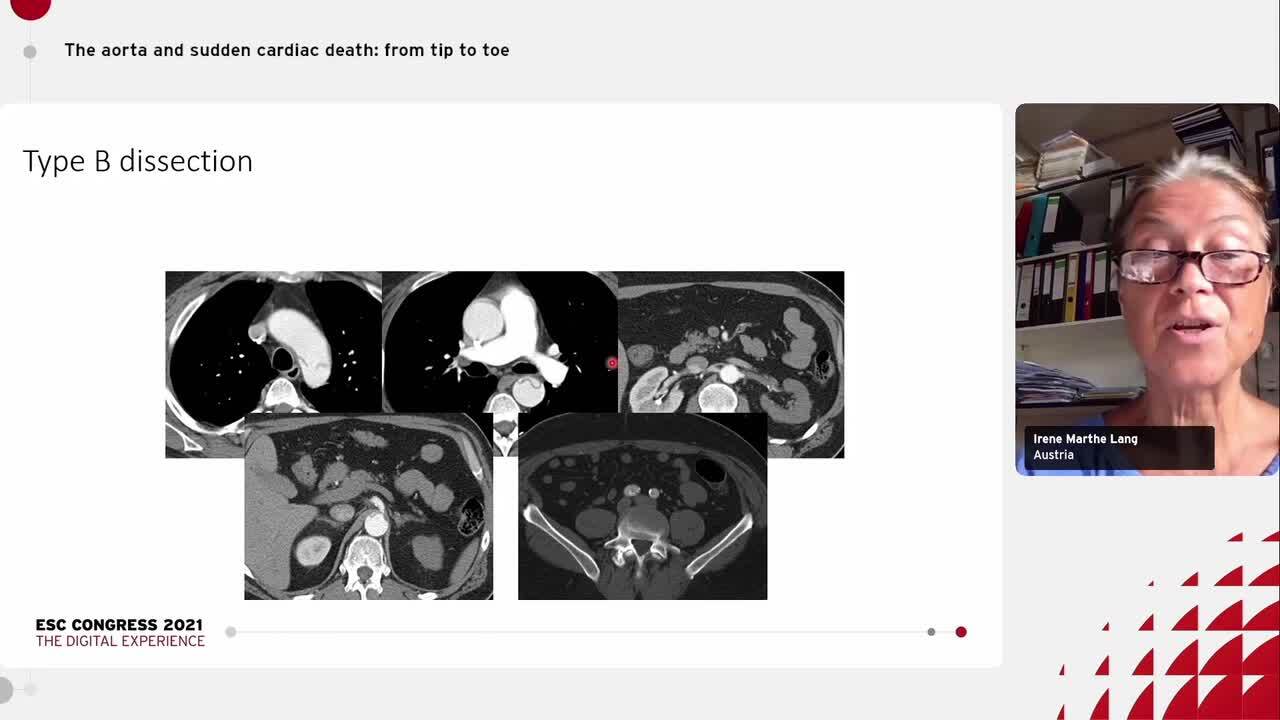

The aorta and sudden cardiac death: from tip to toe – discussion.